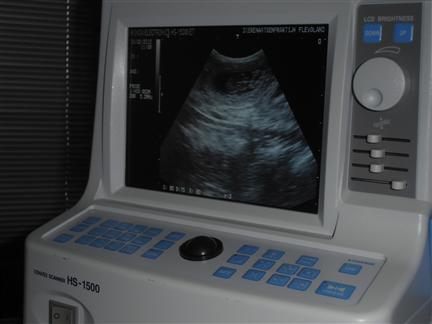

| hier een ander pupje |

nog eens het zelfde pupje |

| Je kon het hartje ook al fanatiek zien kloppen |

op basis van de ontwikkeling van het hartje is de uitgerekende datum op 22 maart 2012 vastgesteld |